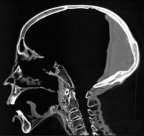

Speculation surrounding the steps following perforation has inspired experimental attempts at excerebration in sheep and human cadavers. The general consensus is that either the brain was macerated by means of the vigorous insertion and rotation of the perforation tool or other similar instrument, or that the brain was simply allowed to liquefy in the hot Egyptian environment. The first method, consistent with the account of Herodotus, is withdrawal of residues on the perforation tool or its like and Macalister (1894) refers to a three-toothed hook pictured in Chabas’ Études sur l’Antiquité Historique (p. 79) that may have been used to this effect.

Similarly, Pirsig and Parsche (1991) suggest that a bamboo rod tied with linen may have sufficed for this piecemeal extraction of semi-liquid brain. Both of these techniques are time intensive, with the rod drawing out little of the brain on each retraction. Alternative to, or in conjunction with, the previous method it has been suggested that the liquefied or semi-liquid brain might be allowed to drain from the cranium by placing the body prone. This process might also be expedited by flushing the cranium with water or other fluids, such as the cedar oil used to dissolve organs in Herodotus’ account of the “second process” of mummification.